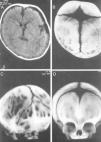

En 72 de 158 (45,6%) casos se dispuso de algún estudio de neuroimagen craneal: 16 radiografías de cráneo, 45 tomografías computarizadas (TC) con o sin reconstrucción 3D (fig. 3) y 11 resonancias magnéticas (RM). Un resultado llamativo del estudio fue la presencia de colecciones pericerebrales de LCR en 36 niños, lo que supone un 23% del total y un 64% de los casos estudiados mediante TC o RM.

En un trabajo previo de nuestro servicio26 y en el estudio actual, se encontró un alto número de pacientes: 36 casos (23% del total) que presentaban en los estudios de TC o RM colecciones extraaxiales de LCR e incluso acúmulos como los observados en la colección pericerebral benigna del lactante. Esta cifra parece elevada, sobre todo teniendo en cuenta que los 36 casos representan el 64% de los niños evaluados mediante estudios de neuroimagen. Existen 2 posibles explicaciones para este hallazgo26. La primera sería que el acúmulo pericerebral de LCR produciría una disminución de la resistencia craneal a la aplicación de presiones externas. Una explicación alternativa consistiría en una redistribución pasiva del LCR dentro del cráneo, que tendería a desplazarse hacia las zonas de menor resistencia.

Para la confirmación diagnóstica de deformación craneal posicional se ha empleado la ecografía de las suturas10. En casos seleccionados, se puede obtener una única radiografía craneal en proyección de Towne, que es suficiente para valorar ambas suturas lambdoideas. No obstante, en caso de duda, el método diagnóstico de elección consiste en la obtención de una TC-3D que permite ver tanto el estado de las suturas como el del cerebro10,28. La RM se emplea sobre todo para evaluar el cerebro y los espacios de LCR en casos con sospecha de patología intracraneal asociada.